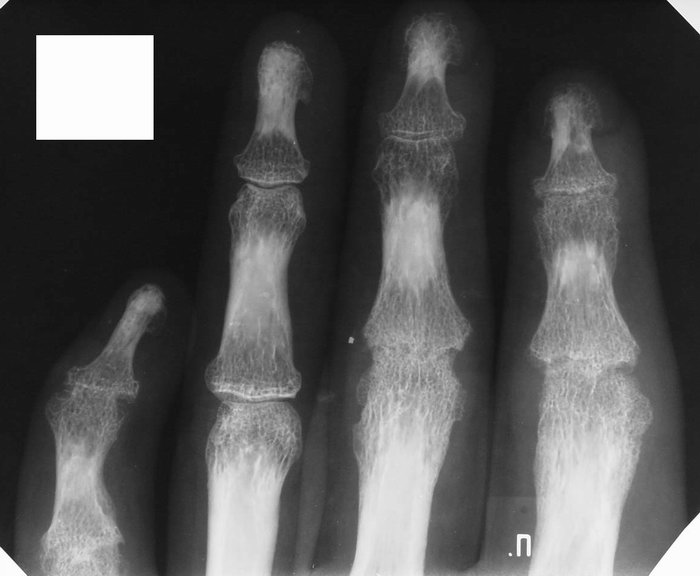

На рентгеновских снимках остеопороз проявляется в виде пятнистой или диффузной редукции костной ткани.

Общим радиологическим признаком для обеих форм остеопороза является высокая прозрачность костей для рентгеновских лучей. В зависимости от типа заболевания участки могут выглядеть как более светлые пятна на фоне нормальной или слегка изменённой костной ткани (пятнистая форма) или как полностью светлая кость (при диффузной форме).

При рентгенографии наблюдается истончение отдельных костных пластин, а структура кости напоминает широкопетлистую сеть с увеличенными ячейками. При этой форме заболевания корковый слой костей остаётся неизменным, хотя в некоторых случаях может наблюдаться разрыхление внутреннего слоя, который превращается в губчатую костную ткань.

Рентгенологическое исследование при диффузной форме остеопороза демонстрирует изменения в губчатой ткани. Она состоит из редких и едва заметных балок, которые почти не задерживают рентгеновские лучи.

При выраженной резорбции кости на снимках выглядят «стекловидными» и не отличаются от окружающих тканей. Корковый слой на протяжении всей кости значительно истончен, и с внутренней стороны может быть заметна продольная исчерченность. Наружный слой кортикального вещества создаёт такую плотную тень на снимке, что кости выглядят, как будто обведены черной тушью.

В отличие от других форм костной атрофии, при остеопорозе размеры и форма костей остаются неизменными. По дифференциальным признакам на рентгенограмме легко отличить остеопороз от костной атрофии.